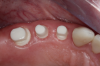

Fig 15. Provisionals 12 weeks postoperatively.

Figure 15

Fig 16. Final restorations (15 weeks postoperatively).

Figure 16

After the preparations were evaluated and accepted by the clinician, provisionals were completed with traditional crown-and-bridge techniques. Then the provisionals were fabricated with a replication stent derived from the diagnostic wax up (Figure 14). The provisionals were well-fitted to both the natural dentition and the ceramic dental implants (Figure 15). The provisional that was fixed to the implant was kept out of occlusion and had a narrow buccal-lingual occlusal table. The smaller occlusal table and short occlusal scheme provided light loading forces and stimulated the bone tissuethe brain detects the stimuli and sends osteoblasts to the area to increase bone density surrounding the implant. The recommendation for the light-loading provisional phase was to have the patient function with the provisionals for 4 weeks.

The final impression appointment follows the light-load phase, provided the implant is stable and the soft tissue is acceptable to the clinician. Polyvinyl putty and light-body impression materials were used in this case; analog casts and final full-zirconia full crowns were fabricated (Figure 16). The patient provided feedback that chewing was comfortable and without food impactions. Keratinized gingival cuff was developed, and natural-tooth contours for the restorations mimicked what is normally found in human dentition. The healed bone surrounding the ceramic dental implant was similar in density and crestal levels in comparison with the adjacent natural teeth, evident in the radiographic evaluation (Figure 17). Final long-term restorations at the gingival crest and restoration interfaces were also consistent in optimum periodontal health and gingival height. Arch-form integrity was upheld and occlusion was managed; osseointegration and light-load principles optimized the success of the restorations, and an acceptable, harmonious esthetic outcome was achieved for the patient.